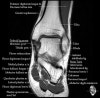

- Axial section

Axial PD fat suppression evaluates the tendons and ligaments of the ankle particularly after acute/subacute injuries. It also is sensitive to talar dome osteochondral defects. Alternatively, a T2 sequence can be used to eliminate magic angle artifact that may occur as the tendons travel around the malleolar turns.

Tibiofibular ligaments

Lateral ankle ligaments

Deltoid and spling ligaments

Tendon(Achilles, Medial, Lateral, Anterior)